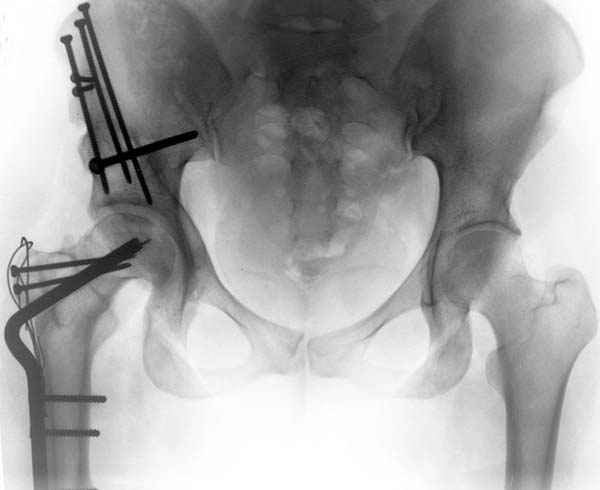

Рис.1 Трехмерная модель тазобедренного сустава с аналогом связки головки бедра. Заметно, что из торца головки выходит капроновый шнур, который с одной стороны прикрепляется к ножке бедренной части модели, а другой его конец, проходя через головку и прикрепляется к вертлужной части модели. Динамометр оказывается не нагруженным, так как аналог связки головки бедра замыкает подвижный узел модели во фронтальной плоскости.

Рис.2 Та же трехмерная модель тазобедренного сустава без аналога связки головки бедра. Пружина динамометра удерживает тазовую часть модели от опрокидывания, поддерживая стабильность так же, как отводящие мышцы обеспечивают ее в отсутствии связки головки бедра.

Модель несовершенна, согласен, однако я экспериментировал и с импровизированной илеофеморальной связкой и ацетабулярной губой. Результат был тот же, подвижный узел замыкался посредством аналога СГБ. Для интереса я прилагаю фото., где сымитированы наружные связки и вертлужная губа, но без СГБ видно по показаниям динамометра, что данные структуры незначительно только на 0.5 кг разгружают аналог отводящих мышц. Почему модель получилась именно такой можно рассказать и подробнее если захотите…